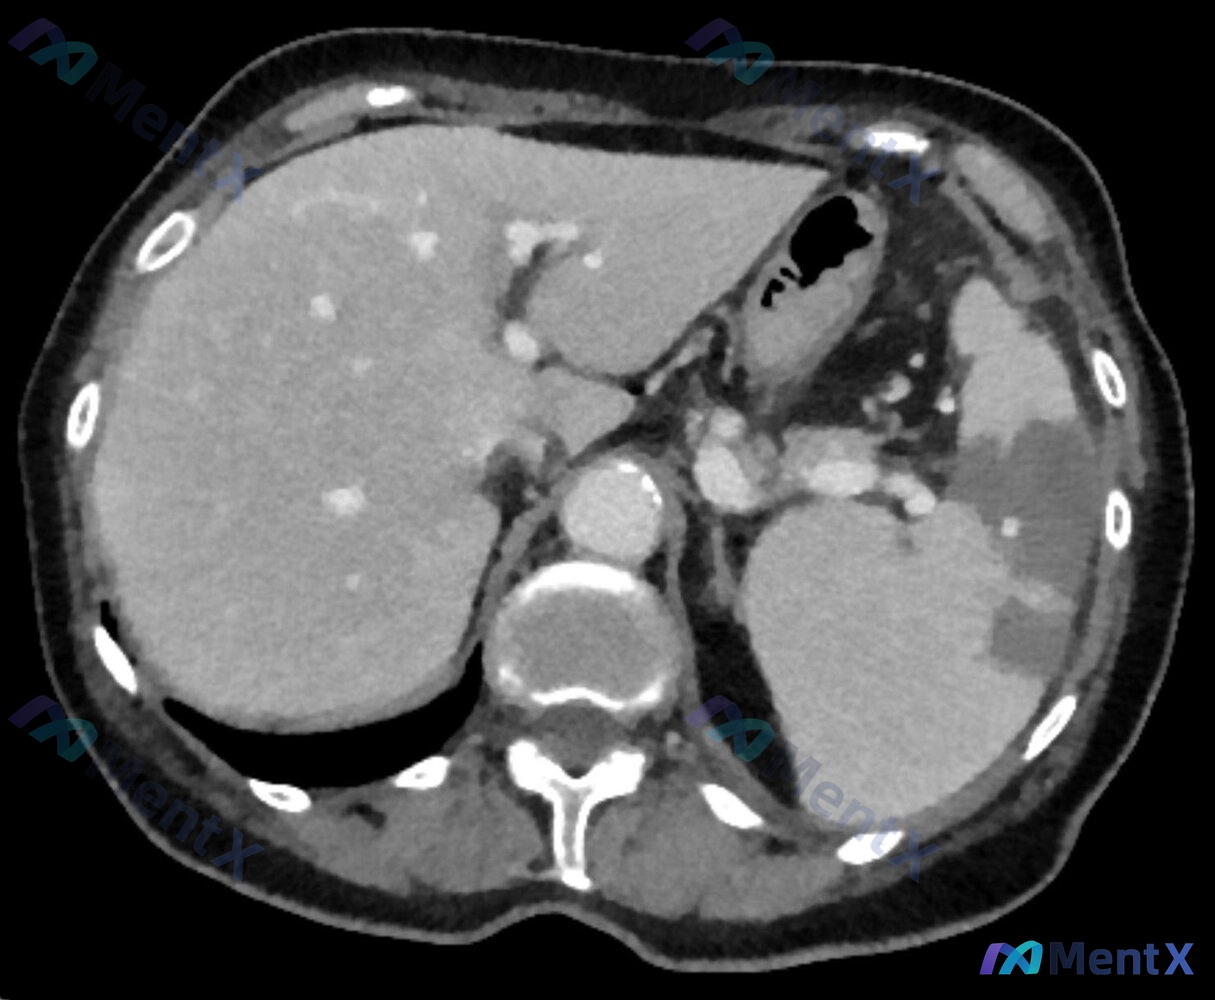

影像表现(腹部增强CT)

这里是关键!

- 脾脏:体积增大,内见多发边界清晰的楔形、片状低密度区,主要在脾外缘,呈“地图样”改变(典型的脾梗死影像)

- 肝脏:肝内可见多发斑片状稍低密度影

- 其他:无明显游离腹腔积液,腹主动脉壁见钙化,无腹膜后肿大淋巴结